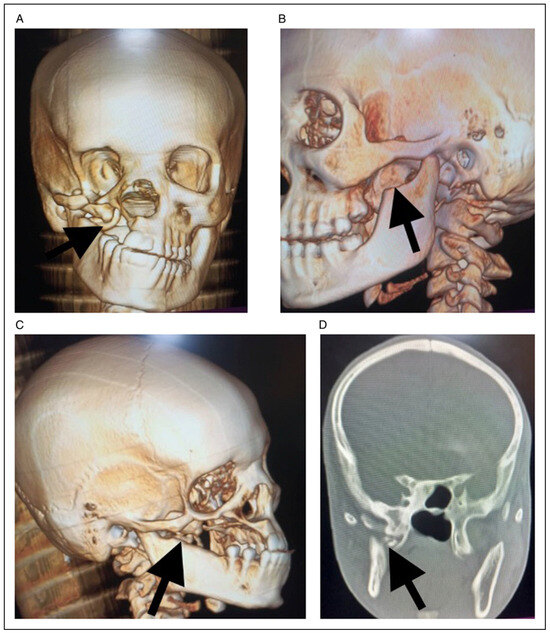

Braimah-Taiwo et al. New Classification System and Treatment Algorithm of Mandibulo-Maxillary Synostosis Related to Noma. Field Experience From Noma Children Hospital Sokoto, Nigeria

by Ramat Oyebunmi Braimah, A. O. Taiwo, H. O. Olasoji, J. N. Legbo, M. Amundson, A. A. Ibikunle, I. K. Suleiman, M. Bala and B. O. Ile-Ogedengbe

Craniomaxillofac. Trauma Reconstr. 2024, 17(4), 279-290; https://doi.org/10.1177/19433875231214071 - 15 Nov 2023

Study Design: This was a retrospective study at Noma Children Hospital, Sokoto, Nigeria, from January 2018 to December 2021. Objective: The main objective of this appraisal was to present Braimah-Taiwo et al.’s new classification system for mandibulo-maxillary synostosis secondary to noma and also [...] Read more.

Study Design: This was a retrospective study at Noma Children Hospital, Sokoto, Nigeria, from January 2018 to December 2021. Objective: The main objective of this appraisal was to present Braimah-Taiwo et al.’s new classification system for mandibulo-maxillary synostosis secondary to noma and also to provide a guide to their treatment. Methods: Noma with mandibulo-maxillary synostosis was the main inclusion criteria. Excluded were cases of acute noma and noma without mandibulo-maxillary synostosis. Data retrieved include demographics of patients and extent of bony ankylosis and mandibulo-maxillary synostosis. Results: A total of 64 patients (30 (46.9%) males and 34 (53.1%) females) were managed. Ages ranged from 6 to 40 years with mean ± SD (18.2 ± 7.6) years. Regarding the new classification system of mandibulo-maxillary synostosis, 6 (9.4%) patients presented with Type 1 (Mild joint obliteration) ± Soft tissue scarring, 24 (37.5%) presented with Type II (Total joint obliteration) ± Soft tissue scarring, 21 (32.8%) presented with Type III (Coronoid, zygoma and maxilla) ± Soft tissue scarring, 4 (6.3%) presented with Type IV (Condyle, glenoid fossa, coronoid, sigmoid notch and zygoma) ± Soft tissue scarring, 7 (10.9%) presented with Type V (Condyle, glenoid fossa, coronoid, sigmoid notch, zygoma and pterygo-maxilla) ± Soft tissue scarring, while 2 (3.1%) patients presented with Type VI (condyle, glenoid fossa, coronoid, sigmoid notch, zygoma, pterygo-maxilla and the orbit) ± Soft tissue scarring. Conclusions: Pattern of tissue destruction in noma patients is complex involving both soft and hard tissues. This new classification will guide surgeons in the effective management of these patients. Full article